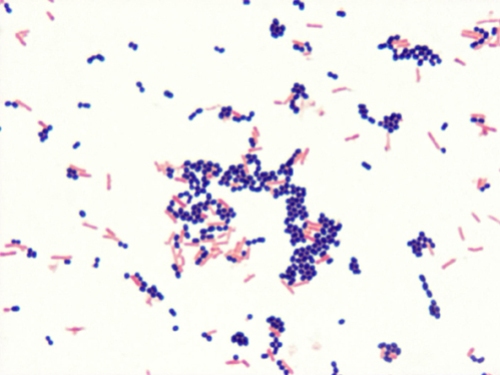

Gram stain control

Taken from an SBA control plate, Gram negative rod (Escherichia coli) which is physically mixed with a Gram positive cocci (Enterococcus faecalis). A good control would be rated as having a strong purple color in the Gram positive cocci and strong red color in the Gram negative rods.